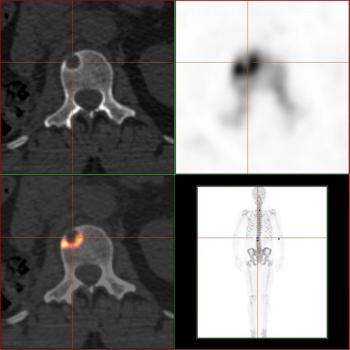

This slide show features images of diffuse osteoblastic bone metastases in a 70-year-old advanced prostate cancer patient, bone metastases in the vertebral column of a kidney cancer patient, and more.